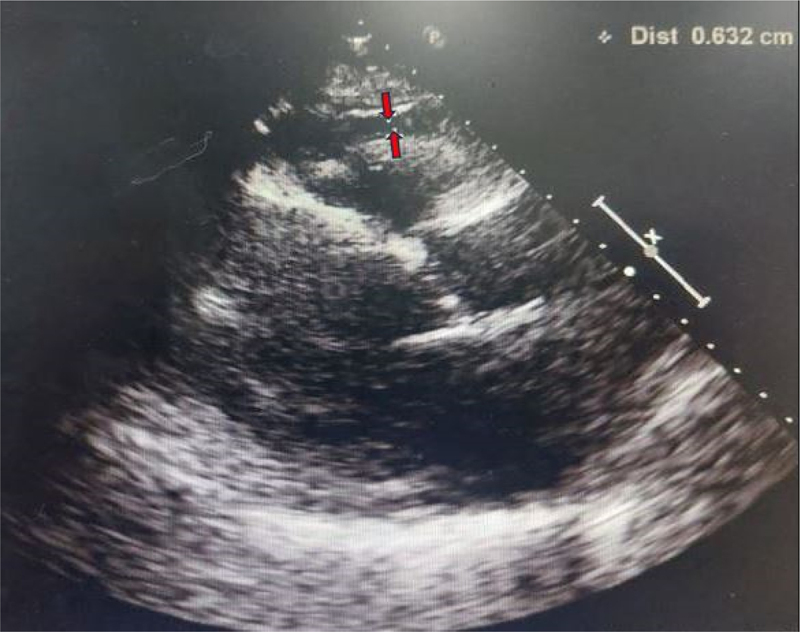

Excessive deposit of epicardial adipose tissue (EAT) were recently shown to be positively correlated with cardiovascular disease (CVD). This study aims to investigate the thickness of EAT and its association with the components of metabolic syndrome among multi-ethnic Malaysians with and without acute coronary syndrome (ACS). A total of 213 patients were recruited, with the thickness of EAT were quantified non-invasively using standard two-dimensional echocardiography. EAT thickness among the Malaysian population was prompted by several demographic factors and medical comorbidities, particularly T2DM and dyslipidaemia. ACS patients have significantly thicker EAT compared to those without ACS (4.1 mm vs 3.7 mm, p = 0.035). Interestingly, among all the races, Chinese had the thickest EAT distribution (4.6 mm vs 3.8 mm), with age (p = 0.04 vs p < 0.001), and overall diastolic blood pressure (p = 0.028) was also found to be associated with EAT thickness. Further study is warranted to investigate its role as a cardiovascular risk marker among Malaysians with ACS.

Abstract Image